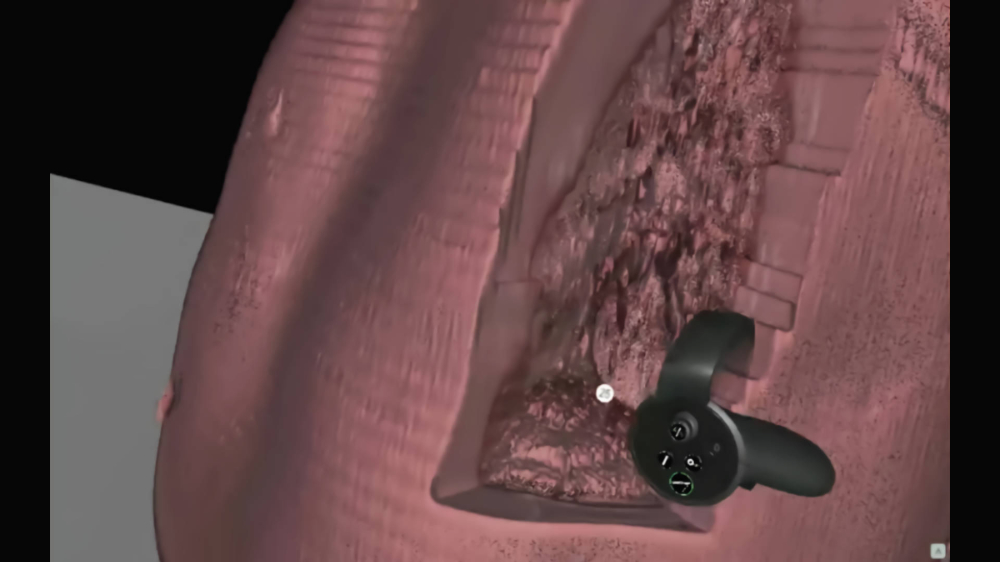

Preview of CT images from

brand new perspective

A modern program for analizing images from the tomograph

Thanks to our program, you will be able to manage lists of your patients in a quick and organized manner, saving time and more efficiently analyzing images from a computer tomograph or magnetic resonance imaging. The application allows you to load photos into the Virtual Reality environment, giving you the opportunity to view and analyze them in a new, unconventional way. Photos displayed in the form of 3D models can be freely rotated and viewed from different angles.